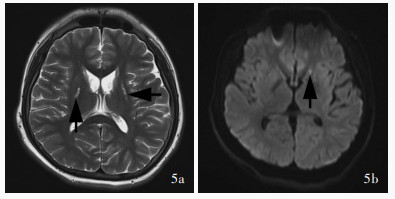

Ji K , Wang W , Lin Y , Xu X , Liu F , Wang D , Zhao Y , Yan C . Mitochondrial encephalopathy due to a novel pathogenic mitochondrial tRNA Gln m. 4349C > T variant. Ann Clin Transl Neurol, 2020, 7: 980- 991.